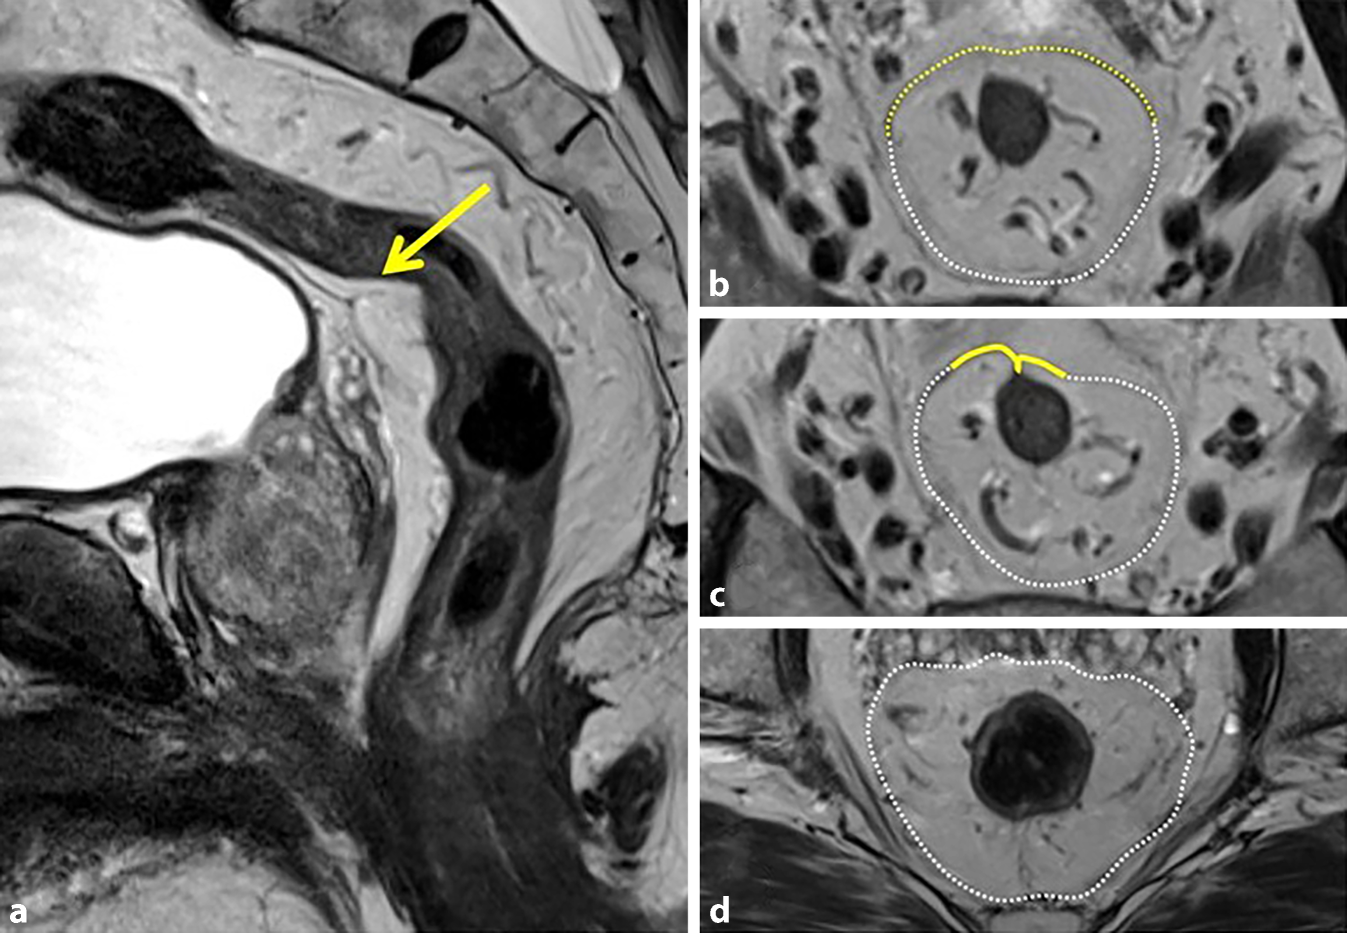

Abb. 5

a Sagittale T2-gewichtete MRT-Bilder, welche die vordere peritoneale Umschlagsfalte bei einem Mann (ohne Rektumkarzinom) auf Höhe der Samenbläschen (gelber Pfeil) zeigen. b Auf der Ebene oberhalb und an der peritonealen Umschlagsfalte (c, gelbe Linie) steigt die mesorektale Faszie (MRF, gestrichelte weiße Linie) dorsolateral auf und bedeckt nur die lateralen und dorsalen Teile des Mesorektums, während das vordere Mesorektum vom Peritoneum (gestrichelte gelbe Linie) bedeckt ist. d Die MRF (gestrichelte weiße Linie) umgibt das gesamte Mesorektum

Die Abschnitte des mittleren und oberen Rektums sind ventral bis ventrolateral von Peritoneum überzogen, während die dorsalen Abschnitte und das untere Rektum extraperitoneal liegen und von der mesorektalen Faszie berandet sind. Auf der T2-gewichteten Sequenz ist die peritoneale Umschlagsfalte als zarte, hypointense Struktur abgrenzbar (Abb. 5a; [13]). Die Unterscheidung zwischen peritonealen und extraperitonealen Abschnitten des Rektums ist für die Stadieneinteilung essenziell: Eine Infiltration der MRF ergibt ein Lokalstadium T3 MRF+, wohingegen die Infiltration des Peritoneums ein Lokalstadium T4a ergibt mit einem erhöhten Risiko einer intraabdominellen Aussaat (Abb. 5b, c).